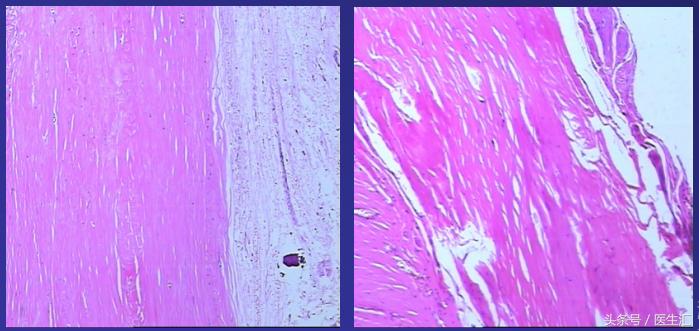

治疗:2011-11-29行心包剥脱术,术中见心包显著增厚,壁、脏层心包粘连紧密,无积液。最致密处位于心脏膈面及右房室沟,心包最厚约10mm,质地坚硬,散在少量钙化。

心包病理:纤维结缔组织增生并玻璃样变,符合缩窄性心包炎改变